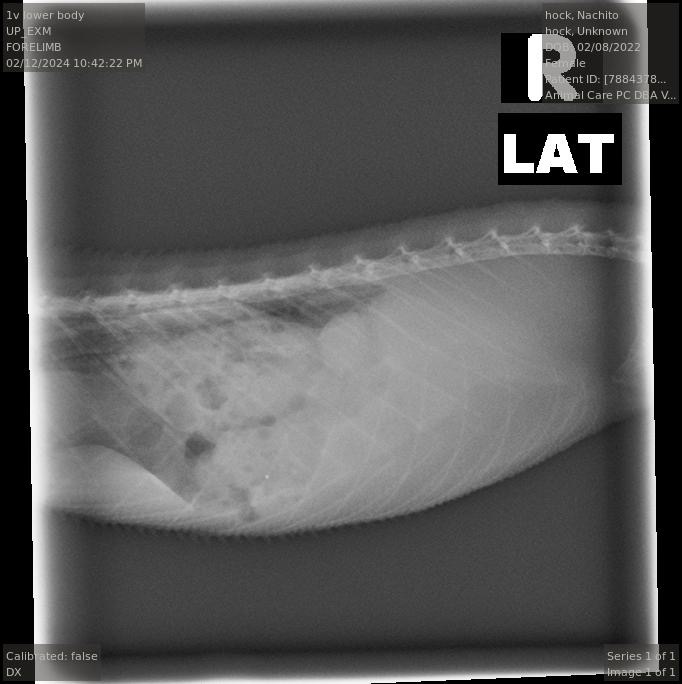

! But today at a vet appointment, Nachito was finally diagnosed with gout. After months of her uric acid levels seeming to be normal, today they came back as elevated.

Other than the uric acid levels and pore, the vet said there was nothing else significant on the X-rays and ultrasound.